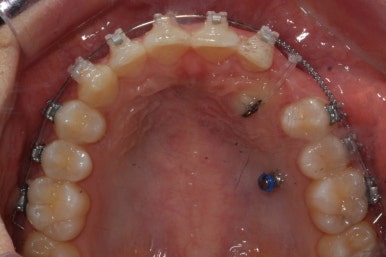

부산매복치아교정 키다리아저씨치과에서 소수술을 마친 모습입니다.

우선 남아있던 유치는 발치를 했고, 매복 송곳니에 장치를 붙인 후 잇몸 밖으로 체인 형식의 연장선만 빼놓았습니다. (두 개의 화살표 중 위쪽 화살표) 매복치아를 적절한 방향으로 요리조리 당겨줘야 하기 때문에 미니스크류를 이용했습니다. (두 개의 화살표 중 아래쪽 화살표)

수평으로 누워있었던 송곳니의 각도가 바로 잡힐 때까지는 계속 미니스크류만을 이용해서 당겨줍니다. 치아는 뼈속에서 헤엄치듯이 조금씩 방향을 잡아갑니다.